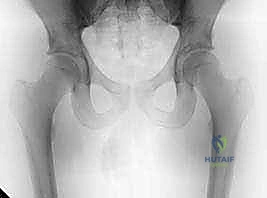

* الأشعة السينية العادية (X-Rays): يتم أخذ صور بوضعيات خاصة (مثل وضعية Dunn View) لرؤية مفصل الورك من زوايا متعددة. تكشف الأشعة السينية بوضوح عن وجود حدبة "كام" أو بروز "كماشة"، وتظهر مدى ضيق المسافة المفصلية (مؤشر على الخشونة).